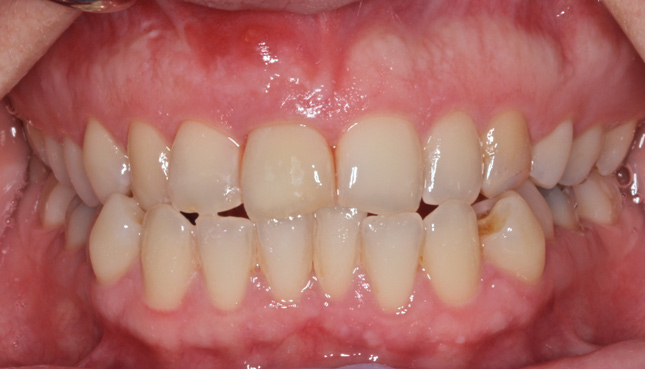

The patient was brought back weekly for 4 weeks for postoperative follow-up. Healing was satisfactory (Figure 18). Four months after implant placement, the final restoration, a porcelain-fused-to-metal screw-retained crown, was inserted at site No. 8 (Figure 19).

Fig 19. Final screw-retained crown on implant at site No. 8.

Figure 19